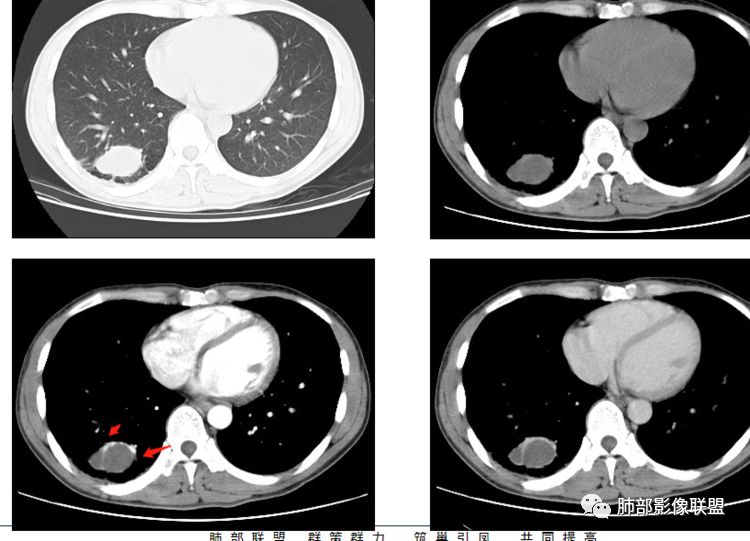

右肺下叶囊性病变,边缘光滑,薄环状强化,内壁较光滑

血管贴边

周围多发长索条

远端有斑片状条带状高密度影,周围肺气肿

附近胸膜增厚,内有血管影

第三,病变旁边胸膜区域有增厚,似乎有些血管增粗,虽然这不是隔离征好发区域;它应该偏内侧一点,但是我们应该最好有重建血管先排除隔离征;从所给图片看,病灶具体走形外面没有看见血管进入,因为是囊性病变嘛。

第四,病变为薄壁环状强化,就两种可能,

1 是病变内为囊性成分,即囊肿,周围病变考虑合并感染;      2 是病变内是干酪坏死,周围是薄壁强化,然后是一点纤维组织,再周围是一些结核的病灶;

但是有些疑惑:

首先周围病变肯定是感染性病变;索条状的,但是囊肿伴这样感染,真的很少见;

其次病变周围有索条、肺气肿,这些慢性病的改变;还有就是形态,似乎是稍长点的形态;这几点就更符合结核的表现,但是周围病灶没有树芽征,都是索条;结核这样子的干酪样坏死,也少见,壁薄呈这样,就一层纤维;附近的血管又这么粗;

但是我们先把方向锁定在炎性病变;囊肿伴感染还是结核,这两个在图片上各自特点都有,从目前条件无法完全典型的分辨出来;但是还是倾向于囊肿合并感染。

结果

晨读病理

支气管囊肿伴感染